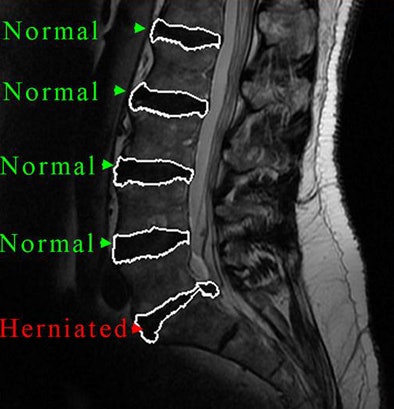

| CAD segments the intervertebral disk material (right) from T2-weighted MR images. |

The CAD's sensitivity for detecting a herniated disk was 93%, with a specificity of 83%. The area under the receiver operator characteristics curve was 92%; agreement with the radiologist not using CAD was 69%.

"The CAD system segmentation algorithm delivered high accuracy with quantitative measurements from the automated system that are highly repeatable, and good agreement with the radiologist," Michopoulou said.

In other results, the algorithm showed highly accurate segmentation performance, with a mean boundary error of less than 1 mm that included both normal and herniated disks, Michopoulou said. Processing time was two seconds per disk for 2D data and 20 seconds per disk for the "pseudo-3D" interpolated data, Michopoulou said.

| CAD output distinguishes normal from herniated lumbar disks. |

Measurement repeatability rose to an intraclass correlation coefficient greater than 0.97 using the method, and both regional features and co-occurrence textural features showed statistically significant differences between normal and herniated disks (p < 0.001).